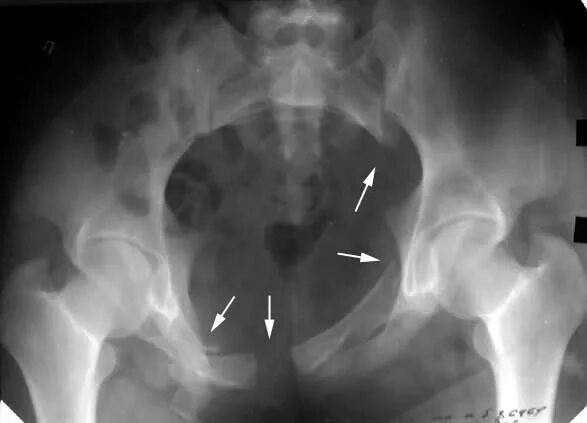

Разрыв крестцово подвздошного сочленения